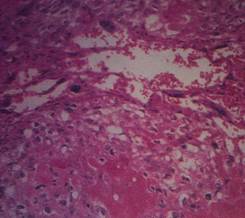

侵蝕性葡萄胎2型 肉眼可見少~中等量水泡,組織有出血壞死,滋養細胞中度增生,部分細胞有分化不良。

3型 腫瘤幾乎全部為壞死組織和血塊,肉眼需仔細才能見少數水泡,個別僅在顯微鏡下才能找到腫大的絨毛,滋養細胞高度增生並分化不良,形成上極似絨毛膜癌。

6、宮切除後,病理檢查可確診。病理特點為葡萄胎組織侵入肌層,滋養細胞增生活躍,組織壞死、出血,可見到絨毛結構。

4.組織學診斷單憑刮宮標本不能作為侵蝕性葡萄胎的診斷依據,但在侵入子宮肌層或子宮外轉移的切片中,見到絨毛結構或絨毛退變痕跡,即可診斷為侵蝕性葡萄胎。若原發灶與轉移灶診斷不一致,只要任一標本中有絨毛結構,即應診斷為侵蝕性葡萄胎。